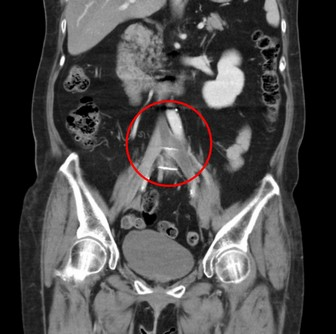

右圖:電腦斷層血管攝影顯示,髂靜脈回流下腔靜脈的入口有阻塞情形。

透過超音波及電腦斷層檢查,郭女士罹患的左側下肢深部靜脈血栓,位於左下髂肢靜脈和下腔靜脈的交叉處,屬於高位血栓,因下腔靜脈是腹部以下血流匯集的血管,包括骨盆、子宮、卵巢、泌尿道的靜脈都會經過,下半身血流的主要幹道被大塊血栓塞住,血液回流差,才會導致骨盆腔以下部位疼痛異常。王惠生醫師與郭女士討論治療方案,隔日就進行機械抽栓手術。

清除血栓後,王醫師用血管內超音波檢查,發現有一段明顯狹窄的區域,推測可能是因長期勞動導致椎間盤突出,往前推的脊椎骨壓迫靜脈往腹部大動脈造成「髂靜脈壓迫症候群」;為了維持日後管徑的暢通,在此處靜脈置放支架。